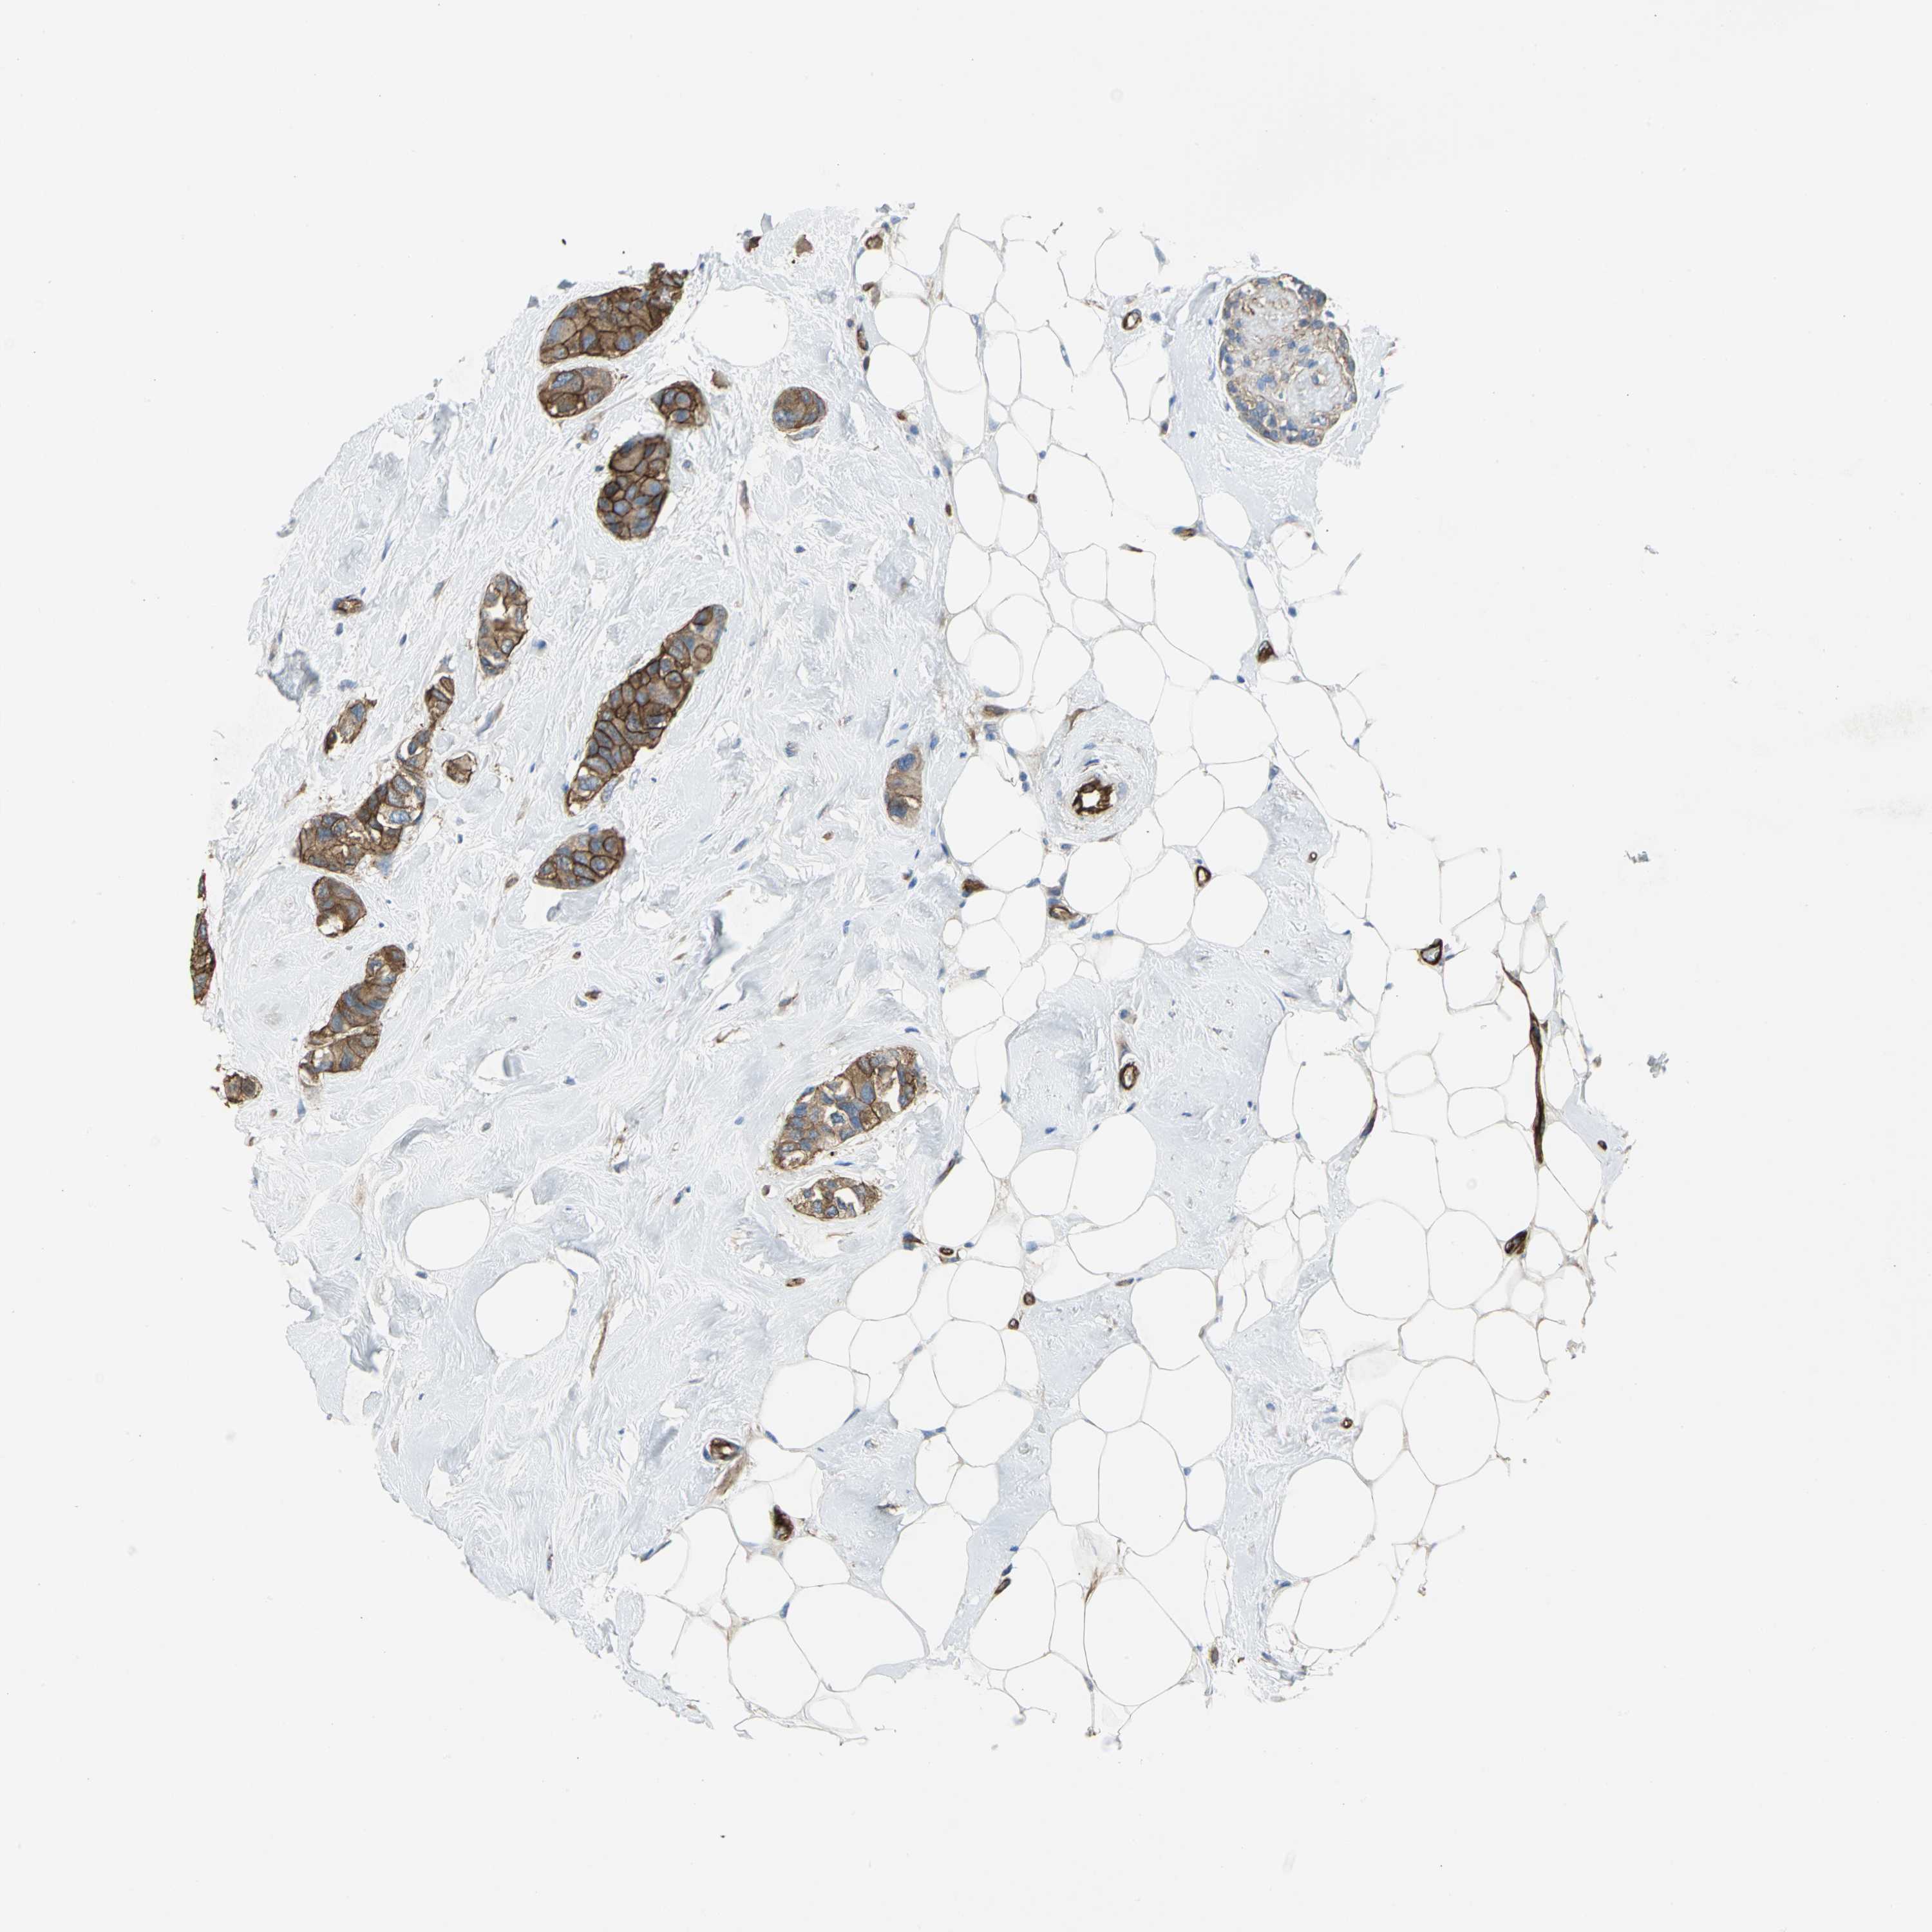

CANCER BREAST CANCER Show tissue menu

BRCA TCGA BRCA VALIDATION PROTEIN EXPRESSION

ANTIBODIES

AND

VALIDATION